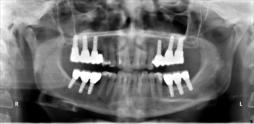

Beispiele für komplexe implantologische Versorgungen aus unserer Gemeinschaftspraxis

(Planung / Endversorgung -- als Röntgenaufnahmen)

C1